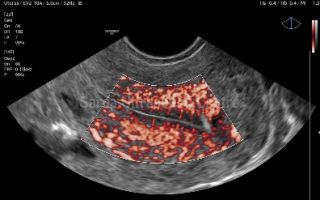

Dedicated 4D curvilinear and transvaginal probes help in more accurate diagnosis in fetal abnormalities and uterine anomalies. Micro-vascular flow imaging picks up smallest of flow on doppler; specially useful in endometrial doppler, torsion, soft tissue masses, arthritis, etc.